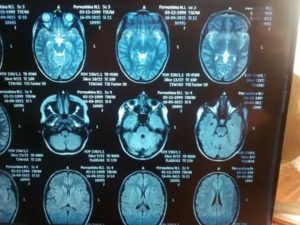

Результаты МРТ исследования врач-диагност получает в трехмерных срезных снимках мозга, а пациент получает изображение на носителе или на почту.

МРТ головного мозга здорового человека показывает целостный орган, без патологических очагов и смещений структур.

Описание заболеваний на сканировании:

МРТ при опухоли.

На снимке новообразование имеет вид несимметричного белого большого пятна, которое имеет рваные края. Это пятно может смещать соседние структуры головного мозга, из-за чего на снимке желудочки и пространства уменьшаются в размере. Когда растет опухоль, появляются новые сосуды. Это видно на ангиографической магнитной ангиографии.

Инсульты.

Ишемический инсульт – это область мозга, где недостает крови. Так, на снимке эта зона выделяется более светлым участком, в отличие от соседних зон. Однако в отличие от новообразования, это светлое пятно будет располагаться в области магистрального сосуда. Если применить ангиографию, то в области ишемии контрастирование снижается.

Геморрагический инсульт – это кровоизлияние в мозговое вещество. На снимке это выглядит как затемнение на МРТ в области магистральной артерии, окруженный темной полосой.

Рассеянный склероз.

Основной признак нейродегенеративного заболевания – это белые пятна на МРТ из-за деструкции миелинового слоя нервных волокон. Безмиелиновые очаги выглядят как совокупность белых пятен, количество которых доходит до 10 в пределах одной области коры.

На начальном этапе развития патологический очаг рассеянного склероза можно спутать с опухолью: эти патологии проявляются белым пятном. Поэтому только повторная магнитная томография через несколько месяцев может показать динамику склероза: количество пятен увеличивается, когда как при опухоли пятно увеличивается в размере.